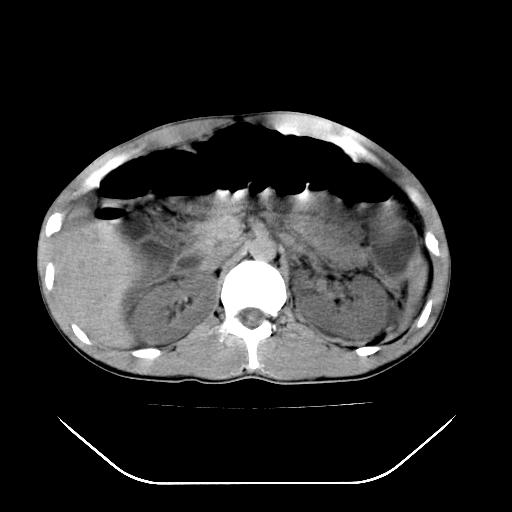

m-25y 高空堕落 12 月5号

12月7号病人尿量200ml/24h 急查双肾ct

左肾挫裂伤并肾周血肿;

12月7号

肝肾间隙可见液区,建议手术探查;

支持:1、左肾挫裂伤并肾周血肿;

2、少量腹水;

3、左肾旋转不良;

4、反射性肠淤张。

反射性肠郁张是指许多原因造成肠道吸收气体和液 功能障碍,也可造成分泌功能与动力的障碍,以致肠道内有过量的气体和液体潴积,有时只有过量的气体潴积。肠道较舒张,但不扩大,或有部分肠道轻度的扩大,这种情况叫做反射性肠郁张 ,这个病人的肠管扩张太明显了。

提示有肠梗阻的可能性?

我不同意守望可西里老师所说的有输尿管的血液凝积一说,首先从这个图像来看输尿管的走行太偏外了,输尿管是肾盂向下延续的部分,开始在腰大肌的外缘,逐渐向内偏移,接近或越过腰椎横突的外端。而守望可可西里老师所指的这段图像位置太靠外了,且总是伴行在一段肠管的前缘。第二,如果有血液的凝积,可造成肾盂肾盏的扩张积水,而这个病人的肾盂肾盏的形态一直很好。

综上所述,考虑1:左肾挫伤并包膜下血肿2:少量腹腔积液3:肠梗阻的可能

除了1:左肾挫裂伤并肾周血肿;

2:少量腹水

第二次ct检查后:临床医生腹水穿刺后考虑肠系膜动脉破裂,后实行剖腹探查:于空肠距离十二指肠90cm处发现肠管破裂,破裂口较小;修补后关腹。